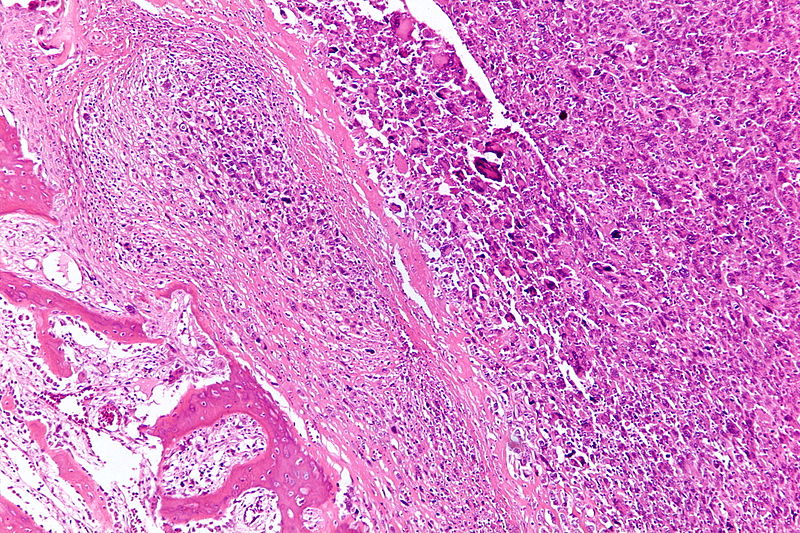

Giant Cell Tumor of the Bone

Giant cell tumor of the bone is composed of multinucleated giant cells and stromal cells that occur in young adults.

Giant cell tumor of the bone typically arises in the epiphysis of long bones, usually the distal femur or proximal tibia.

Radiology of giant cell tumor of the bone classically shows a “soap-bubble” appearance on x-ray.

Giant cell tumors of the bone are locally aggressive, and they may recur after surgical removal.